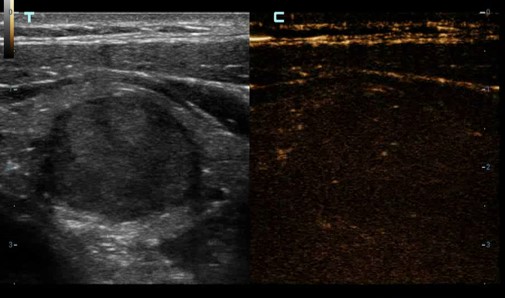

Kontrastné zobrazovanie - UWN+ Kontrastné zobrazovanie: Ultraširokopásmové nelineárne plus kontrastné zobrazovanie

Kontrastné zobrazovanie QA - UWN+ Softvér na analýzu kvantifikácie kontrastu.

UWN+ (Ultra-Wideband Non-linear) kontrastné zobrazenie - CEUS: Excelentná citlivosť na kontrastnú látku aj s minimálnym signálom. Dlhší perfúzny čas s nižším MI. Lepšia vizualizácia perfúzie v jemných cievach s MFE ( Micro Flow Enhancement ). Presná diagnostika benígnych a malígnych tumorov. Výrazne zvyšuje mieru detekcie drobných lézií.

UWN+ (Ultra-Wideband Non-linear) kontrastné zobrazenie - CEUS: Excelentná citlivosť na kontrastnú látku aj s minimálnym signálom. Dlhší perfúzny čas s nižším MI. Lepšia vizualizácia perfúzie v jemných cievach s MFE ( Micro Flow Enhancement ). Presná diagnostika benígnych a malígnych tumorov. Výrazne zvyšuje mieru detekcie drobných lézií.

UWN+ (Ultra-Wideband Non-linear) kontrastné zobrazenie - CEUS: Excelentná citlivosť na kontrastnú látku aj s minimálnym signálom. Dlhší perfúzny čas s nižším MI. Lepšia vizualizácia perfúzie v jemných cievach s MFE ( Micro Flow Enhancement ). Presná diagnostika benígnych a malígnych tumorov. Výrazne zvyšuje mieru detekcie drobných lézií.

UWN+ (Ultra-Wideband Non-linear) kontrastné zobrazenie - CEUS: Excelentná citlivosť na kontrastnú látku aj s minimálnym signálom. Dlhší perfúzny čas s nižším MI. Lepšia vizualizácia perfúzie v jemných cievach s MFE ( Micro Flow Enhancement ). Presná diagnostika benígnych a malígnych tumorov. Výrazne zvyšuje mieru detekcie drobných lézií.

Kontrastné zobrazovanie - UWN+ Kontrastné zobrazovanie: Ultraširokopásmové nelineárne plus kontrastné zobrazovanie

Kontrastné zobrazovanie QA - UWN+ Softvér na analýzu kvantifikácie kontrastu.